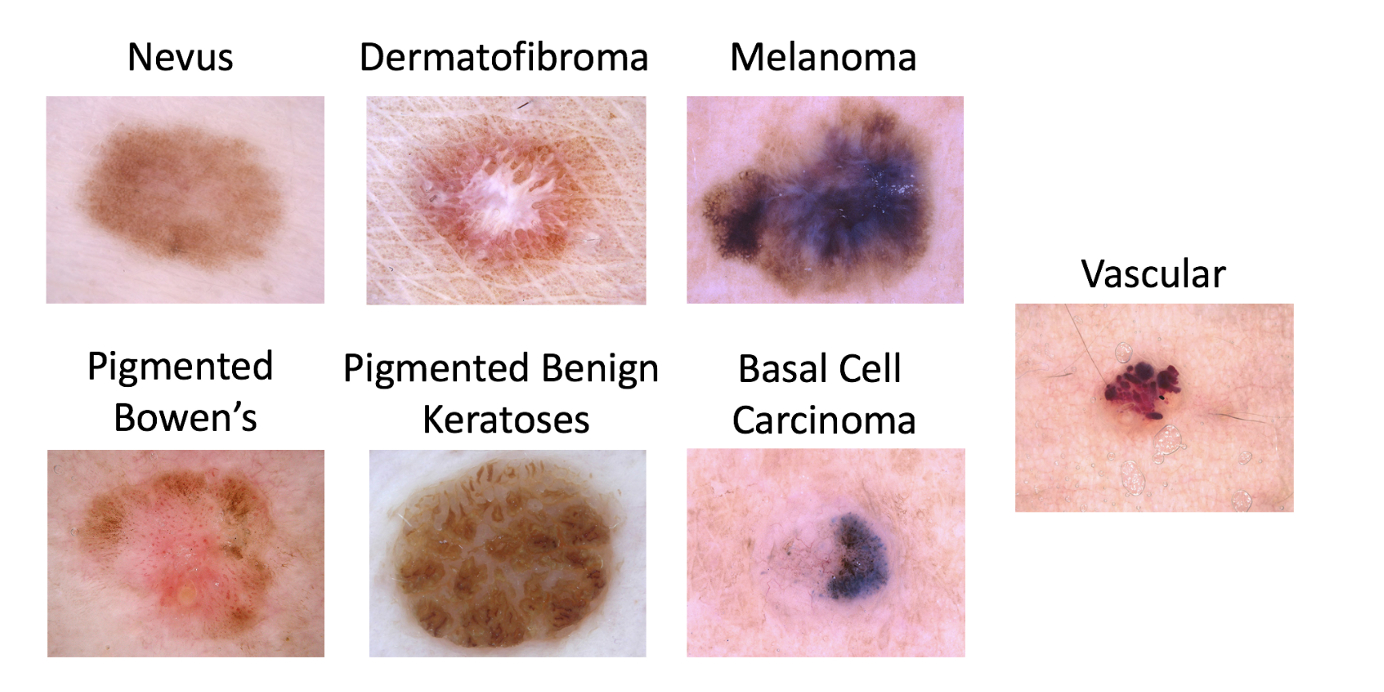

(The full list of lesion types types to classify in the ISIC dataset. We’ll be focusing on Melanoma vs. non-Melanoma)

(The full list of lesion types types to classify in the ISIC dataset. We’ll be focusing on Melanoma vs. non-Melanoma)